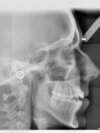

Téléradio